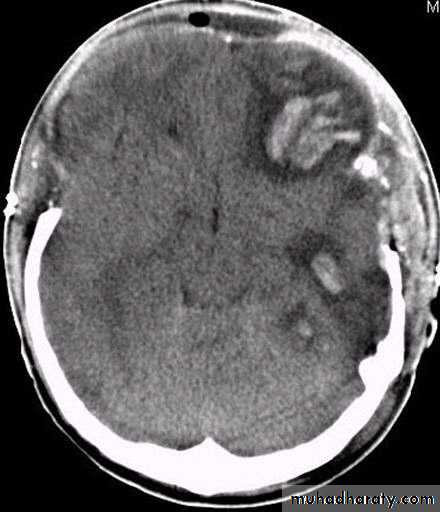

b. Subdural Haematoma

They are the most common intracranial mass lesions resulting from head trauma.

They are classified depending on how long they take to present clinically following the injury into:

Acute Subdural Haematoma: less than 3 days

Subacute Subdural Haematoma: 4-21 days

Chronic Subdural Haematoma more than 21 days.

Acute Subdural Haematoma

Usually due to MORE SEVER high velocity trauma and thus associated with a poorer outcome.

Source of bleeding (haematoma): include:

Most result from torn bridging veins or focal tears of a cortical artery.

Cortical lacerations or contusions.

Bleeding from tears in the dural venous sinuses.

Clinical Picture: patient will present with a picture similar to that of an extradural haematoma, but there is persistent loss of consciousness with no lucid interval.

Ct scan will show a concave hyperdence collection because blood follows the subdural space over the convexity of the brain.

Acute Subdural Haematoma are rapidly evolving lesions and early evacuation via craniotomy is mandatory.